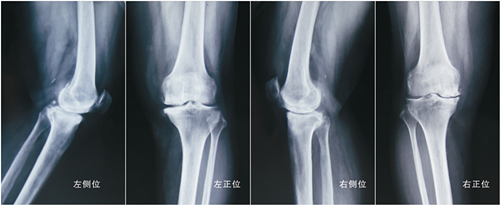

�Ƕ��Ƹ����ν�ѩ��鷿ͼƬ

��ǰXƬʾ��˫��ϥ�ؽڼ�϶���Ա�խ�����γɣ��ؽ��ڷ�����

��ǰ����˫��ؽ����ر��Σ��ʡ���Ȧ�ȡ�